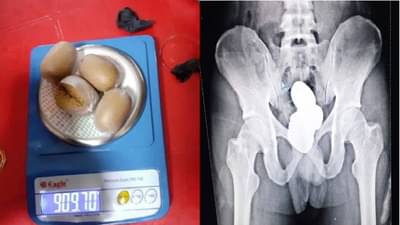

जवानांनी अखेर मोहम्मद शरीफला सोक्यूरिटी होल्ड एरियात आणलं. तिथे त्याची कसून चौकशी करण्यात आली. पण तरीही त्याच्याकडून समाधानकारक उत्तर मिळत नव्हते. अखेर जवानांनी प्रवाशाच्या शरीराच्या खालच्या भागाचा एक्स-रे काढण्याचा निर्णय घेतला. त्यानंतर एक्स-रेचा रिपोर्ट बघून जवान हैराण झाले. कारण त्यामध्ये प्रवाशाच्या पोटात गोल-गोल 4 पॅकेट दिसत होते.

सुरक्षा कर्मचाऱ्यांनी याबाबत त्याला विचारलं असता अखेर त्याने सर्व खरं सांगितलं. त्यावेळी त्याने ते चार पॅकेट्स सोन्याच्या पेस्टचे आहेत, असं सांगितलं. त्याच्या कबुली जाबाबानंतर शरीरातून सोन्याची पेस्ट काढण्यात आली. त्या सोन्याची पेस्टचं वजन केलं असता 909.80 ग्रॅम आलं. या सोन्याच्या पावडरची किंमत तब्बल 42 लाख इतकी आहे. या प्रकरणाचा पुढील तपास सध्या सुरु आहे.